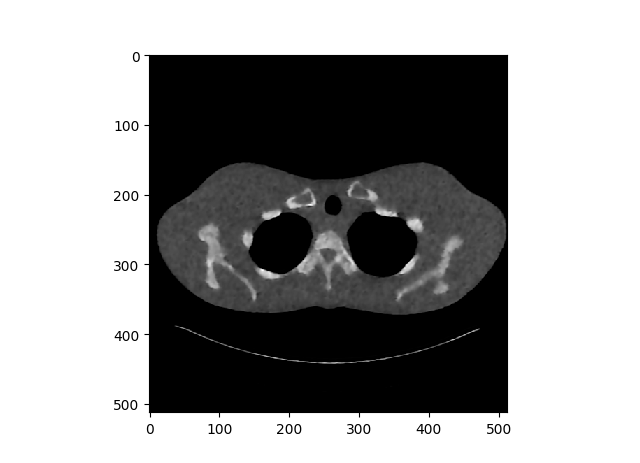

Again, the experimental setup is extremely simple, on the left, we have the original image, and on the right we have the contaminated image. To be more specific, I added uniform distribution noise, we can do this by the code below.

Red Line → Creating a Uniform Noise that we are going to add to the image.

Left → Original Lung CT Scan Image

Middle → Contaminated Image with uniform distribution noise

Right → Denoised Image

In general the network seems to denoise the image correctly, however the produced image have some sharp parts that makes the image bit synthesized.